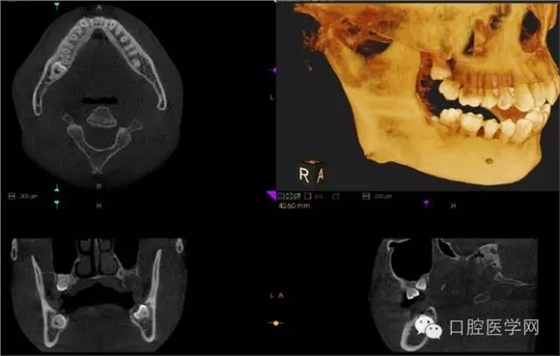

4.阻生牙

最常見(jiàn)于下頜第三磨牙

X線表現(xiàn):確定阻生牙的位置;確定阻生方向;牙根數(shù)目和形態(tài);阻生牙有無(wú)齲齒和根尖情況;與第二磨牙的關(guān)系;與下頜管的距離和磨牙后間隙的大小。